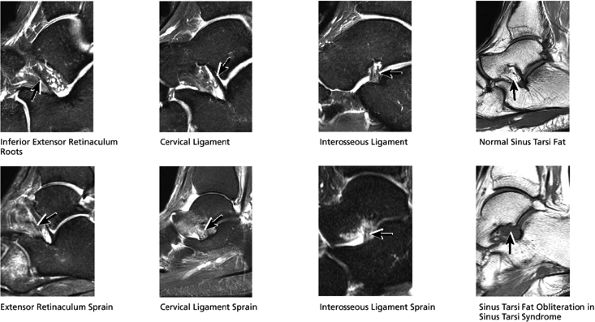

Sinus tarsi ligaments (the extensor roots, interosseous ligament, and cervical ligament)

FIGURE 5.36 Sinus Tarsi Ligaments.